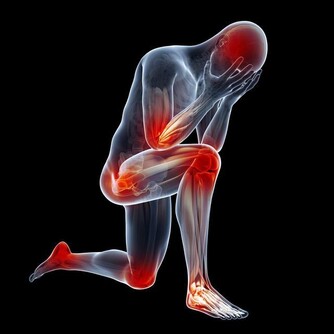

三月初,我的頸椎出了一點問題,整個人的精神狀態都很不好,睡覺不舒服,也不能長期坐在電腦面前。

我在想著,我還這麼年輕,頸椎怎麼就開始出問題了?那以後我怎麼辦?

可是我又非常清楚,長期在電腦面前工作,頸椎出問題也在預料之中。

再想起頸椎不舒服的那段時間裡,我明白這是對我的一種預警,警告著我:如果你再這樣下去,你的頸椎真的會出問題的。